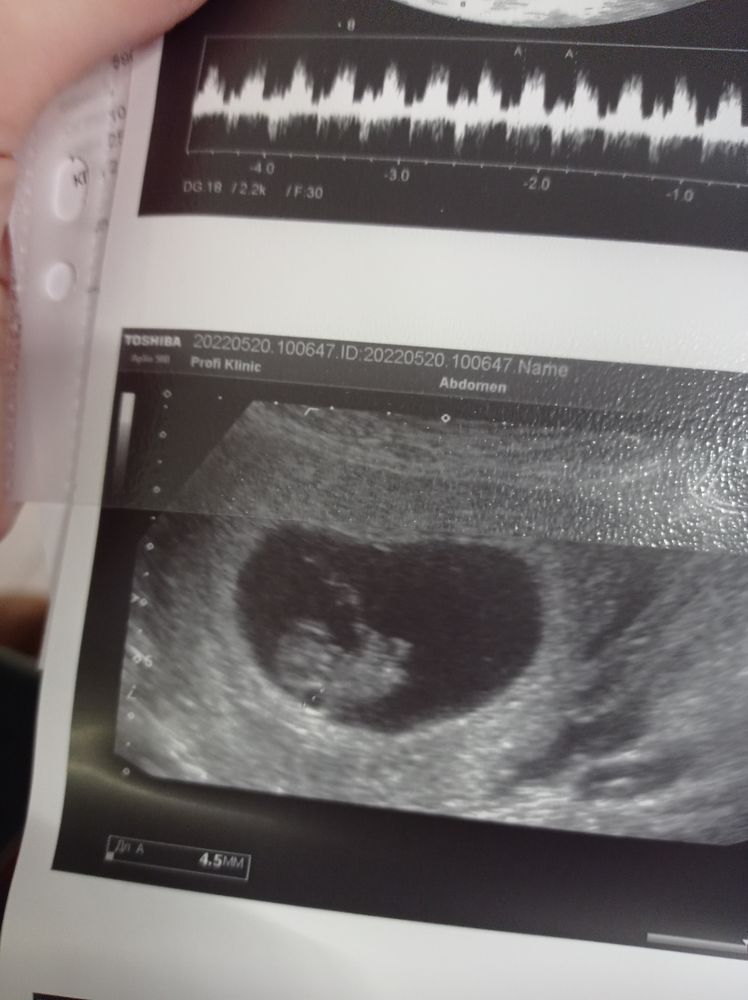

А фото то в форме сердца

Алиса, да похоже на сердечко узистка тоже сказала